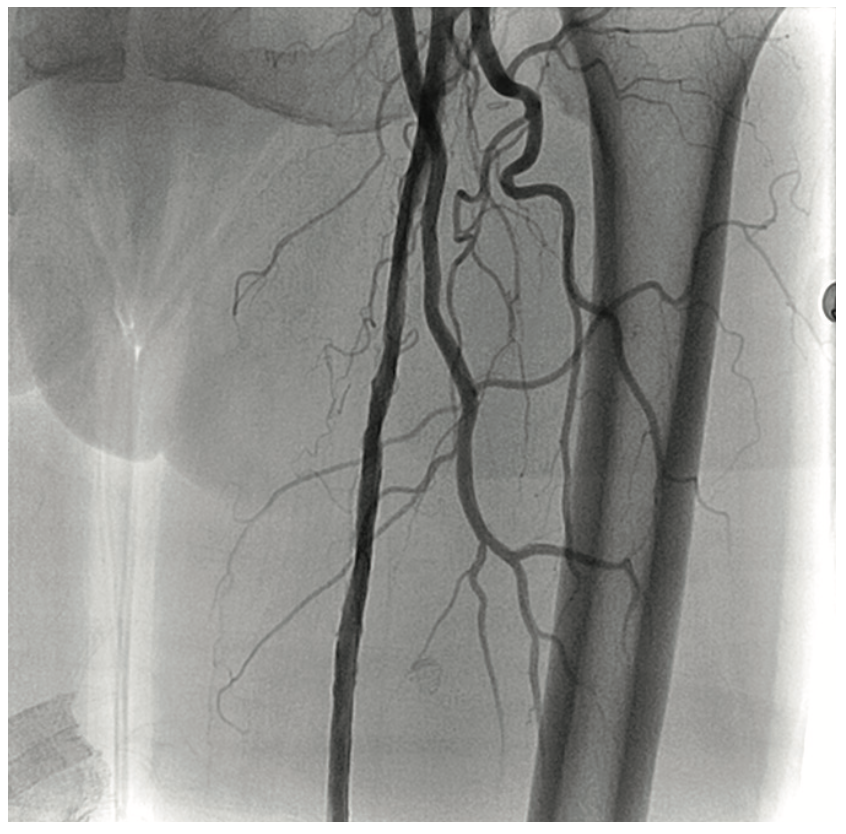

A 90-year-old woman presented with CLI of her left foot. She suffered from claudication beginning 12 years ago. Six months prior, she developed an ulcer on her foot and shortly thereafter, underwent femoral popliteal bypass. Her symptoms recurred and repeat fem-pop surgery was performed at that time. It immediately failed and she had a cadaveric vein placed as a fem-pop conduit, which again occluded and after two revisions of the fem-pop bypass, she was told five months prior to her current presentation that she would not be able to have any further intervention on her leg. At that time, it was suggested she go to hospice. A medial 1 cm x 6 cm foot ulcer was noted on examination, but the patient refused any intervention. Six weeks later, with insistence from the wound care center, and with the patient’s second and third digit now black on that foot, the patient permitted an evaluation for possible limb salvage. The examination showed that the foot was now cool and the second, third, and fourth digits were bluish-black. No pedal pulses were present. The patient was approached via the contralateral groin, and the angiogram revealed her native SFA and graft to be occluded at the origin (Figure 8). With the thought that there was a likelihood of thrombus in the vessel, we utilized the CrossLock LP and crossed the occlusion down to the tibial vessels with a Command wire (Abbott Vascular) wire (Figures 9-10). With some suggestion of thrombus in the digital arteries, 3 mg of tPA was administered locally. A .9 laser was used and subsequent balloon angioplasty was performed using embolic protection (Figures 11-12). The fluoroscopic time was 25.2 minutes and contrast was 273 cc. At the end of the procedure, the patient had 2-vessel infrapopliteal flow and several hours later, was seen by the orthopedic surgeon for metatarsal surgery. The surgeon stated that all the toes were now pink, the patient had palpable pedal pulses, and although it was very likely that some amount of amputation may be necessary in the second and third toe, nothing was removed, and the patient was discharged the next day.